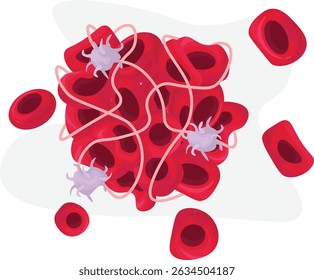

TTPとはTTPについてTTPについて知っておきたいこと Understanding TTP サノフィ株式会社 Sanofi。

5,800点を超える血栓のイラスト素材、ロイヤリティフリーのベクター素材グラフィックスとクリップアート - iStock血管, 血小板, 心臓。

5,800点を超える血栓のイラスト素材、ロイヤリティフリーのベクター素材グラフィックスとクリップアート - iStock血管, 血小板, 心臓。

5,800点を超える血栓のイラスト素材、ロイヤリティフリーのベクター素材グラフィックスとクリップアート - iStock血管, 血小板, 心臓。

5,800点を超える血栓のイラスト素材、ロイヤリティフリーのベクター素材グラフィックスとクリップアート - iStock血管, 血小板, 心臓。

血液凝固と線溶こんにちは✨薬剤師ロクガツです。 今回は血液凝固と線溶系についてのまとめです。 止血機構に関わる ✔︎血友病✔︎DIC 播種性血管内凝固✔︎ITP 特発性血小板紫斑病✔︎TTP 血栓性血小板減少性紫斑病の病態もザックリまとめました。

5,800点を超える血栓のイラスト素材、ロイヤリティフリーのベクター素材グラフィックスとクリップアート - iStock血管, 血小板, 心臓。